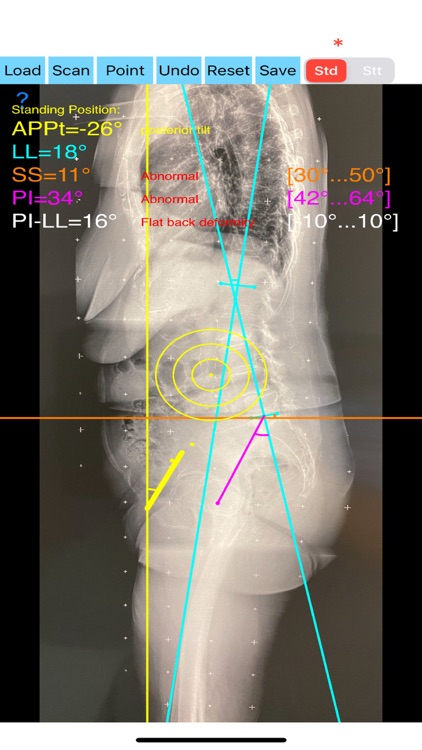

App Screenshots

Evaluation of functional spinopelvic imaging in lateral radiographs in sitting and standing positions is of importance, especially in patient before total hip replacement surgery. Patients with concomitant hip and spine pathology undergoing primary total hip were identified as being at high risk for dislocation. Instability-prone patients arhtroplasty (THA) should appropriately assessed for the presence of deformity and abnormal spinopelvic mobility. The preoperative planning for THA should encompass evaluation of functional spinopelvic imaging in lateral radiographs in sitting and standing positions. Before planning cup position the surgeon should taken into account also anterior pelvic plane (APP) the coronal (functional) plane and the anterior pelvic plane tilt APPt or pelvic tilt and abnormal spinopelvic mechanics from standing to sitting.

The App is software aimed for orthopaedic surgeons, and allow to:

- mark certain points at the image of X-ray, and calculate at once the anterior pelvic plane tilt (APPt) or pelvic tilt , Pelvic incidence (PI), Sacral slope (SS), Lumbar lordosis (LL), Pelvic incidence Angle (PI) minus Lumbar lordosis Angle (LL)(PI–LL).

-to classify the patient into one of four Categories of the Hip-Spine Classification (1A,1B,2A,2B) by integrating spinal alignment (spinal deformity defined at PI-LL mismatch >10 degree(1)

-cases are categorised to group-specific recommendations for acetabular cup position respectively thus with minimal measurements will effectively identify the complex “hip-spine” THA patient at high risk for postoperative instability (1).